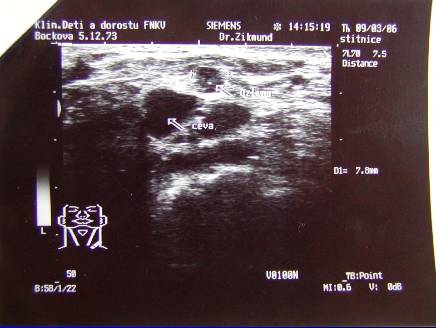

1.Recidiva Ca mammae (pac. L.B.. tumor. markery, UZ, CT, CT-PET, exstirpace susp. uzliny-biopsie)

Recidiva Ca mammae (pac.L.B. tumor. markery, UZ, CT, CT-PET, exstirpace susp.uzliny-biopsie)

Recidiva Ca mammae (pac.L.B.. tumor. markery, UZ, CT, CT-PET, exstirpace susp.uzliny-biopsie)

Recidiva Ca mammae (pac. L.B. tumor. markery, UZ, CT, CT-PET, exstirpace susp.uzliny-biopsie)